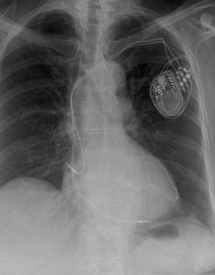

Pacemakers

Pacemakers are most commonly required for patients with a history of collapse or dizzy spells, when ECG monitoring shows that this is due to a slow heart rate. A pacemaker comprises of two main components, the "pacemaker box" which contains a battery and electrical circuit, and the pacing leads (usually one or two leads are required) which are passed along a blood vessel to the heart. The wires can sense when the heart beats normally and if the heart beats too slowly they can produce an electrical impulse to stimulate the heart. The pacemaker box is usually sited under the skin on the upper chest below the collar bone. The procedure is performed under local anaesthesia with sedation if needed. Patients usually need to stay one night in hospital.

A new type of pacemaker, known as a biventricular pacemaker or cardiac resynchronisation therapy is available for certain patients with heart failure. This usually requires 3 leads and improves the timing of the heart which usually leads to improved quality of life and has been shown to prolong life. These pacemakers are only suitable for certain individuals.

Another form of specialist pacemaker called an implantable cardiac defibrillator (ICD) can be implanted in patients who have survived a cardiac arrest or in patients who have had ventricular arrhythmias (fast heart rhythms from the bottom chambers of the heart). The lead detects abnormal rhythms and depending on how the device is programmed the ICD can try to rapidly pace the heart to stop the arrhythmia but if that is not effective it will then shock the heart to restore a normal heart rhythm. An ICD can be combined with a biventricular pacemaker (BiV-ICD) in selected patients with severe heart failure to improve symptoms and improve mortality.